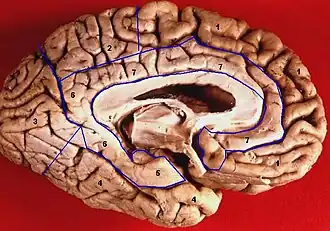

![]() Medial view of left cerebral hemisphere. Parahippocampal gyrus shown in orange. | |

- Medial surface of left cerebral hemisphere. Parahippocampal gyrus shown in orange.